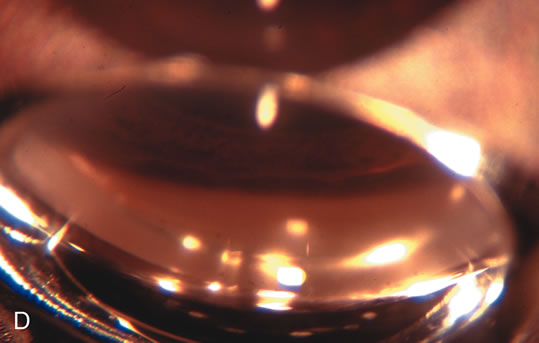

Fig. 4. Viscocanalostomy with deep sclerectomy and phacoemulsification. Nonpenetrating filtration procedures (NPFS) may be combined with phacoemulsification. Patients with mild disc damage and a history of limited topical drug therapy are the best candidates. Patients who require an IOP in the low teens are not good candidates for NPFS. By definition, NPFS is designed to lower IOP without penetrating into the anterior chamber, thereby avoiding the complications associated with trabeculectomy. Viscocanalostomy is intended to allow aqueous to percolate through a trabeculodescemetic membrane into a subscleral cavern created by the deep sclerectomy. The aqueous diffuses from the cavern into the dilated ostia of Schlemm's canal and into the episcleral venous plexus. A. Fashion a uniform 300-micron superficial scleral flap 1 mm into clear cornea. B. Construct a second 600-micron deep flap that facilitates the unroofing of Schlemm's canal, seen as the darker area. C. Use viscoelastic to dilate the ostia of Schlemm's canal. The major problem with viscocanalostomy is the eventual closure of the ostium decreasing flow to the episcleral plexus. D. Dissect the deep flap anteriorly into clear cornea creating the trabeculodescemetic membrane. This membrane is clearly seen between the scleral spur and the bend of the deep flap. The integrity of this membrane ensures the nonpenetrating portion of the surgery. Another problem with NPFS is the eventual fibrosis of this initially transparent membrane requiring goniopuncture. E. Deep sclerectomy gets its name from removal of the deep flap. Removal of this flap creates the potential subscleral space for accumulation of aqueous before it enters Schlemm's canal and exits the episcleral venous plexus. After removal of the deep flap, the superficial flap is sutured into place and conjunctiva closed. Approximately half of these procedures develop a shallow bleb.

CATARACT EXTRACTION ALONE REDUCES IOP IN MOST EYES WITH ANGLE-CLOSURE GLAUCOMA